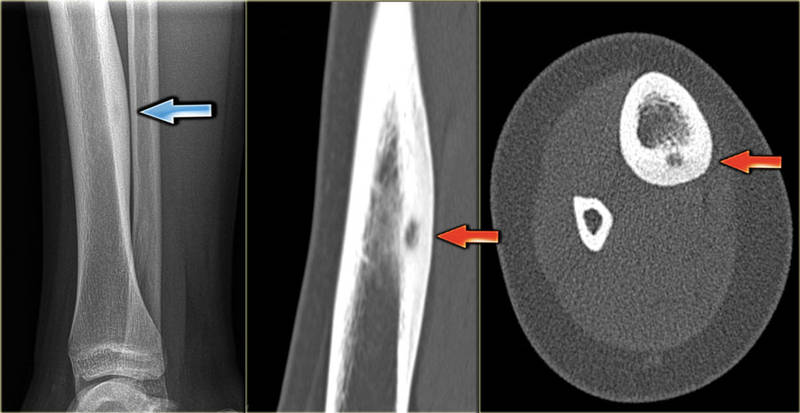

В первую очередь пациент направляется на рентгенографическое обследование. Снимки, обычно сделанные в двух проекциях, выявляют вид образования за границами кости (плотное или губчатое) и наличие разрушений в прилегающих костных тканях. Если опухоль небольшая, то рентген бывает неэффективен. В таких случаях назначают КТ, которая точнее информирует о степени однородности новообразования и его местонахождении. МРТ более точно определяет вид остеомы. Например, кости лодыжки (таранная и пяточная) или кости стопы очень хорошо визуализируются с помощью МРТ.

К гиперпластическим относятся остеомы, имеющие структуру нормальной костной ткани. Они локализуются на костях черепа (на лбу, затылке, за ухом), в стенках придаточных пазух носа (справа и слева). Нередко сдавливают близко расположенные к ним органы, очень часто осложняются нарушением зрения и припадками эпилепсии. Остеоидные остеомы – костные новообразования, отличающиеся от структуры здоровой костной ткани. Остеоиды состоят из богатой сосудами остеогенной (Osteogenus) ткани, беспорядочно расположенных костных балочек и зон остеолиза (участков разрушенных костных тканей). В большинстве случаев не превышают в диаметре 10 мм. Такие опухоли не развиваются на костях головы и грудины. Остеоидные остеомы локализуются преимущественно на длинных трубчатых костях нижних конечностей. Чаще всего поражают большие и малые берцовые, тазобедренные кости (более чем в 60% случаев).

Эностозы (называемые еще костным компактным островком) прорастают в костномозговой канал, как правило, бывают одиночными (исключением является остеопойкилоз, наследственное заболевание при котором отмечаются множественные эностозы). Очаг эностоза в ряде случаев приводит к заращиванию костномозгового канала. Такие опухоли развиваются без симптомов и обнаруживаются случайно на рентгеновских снимках.